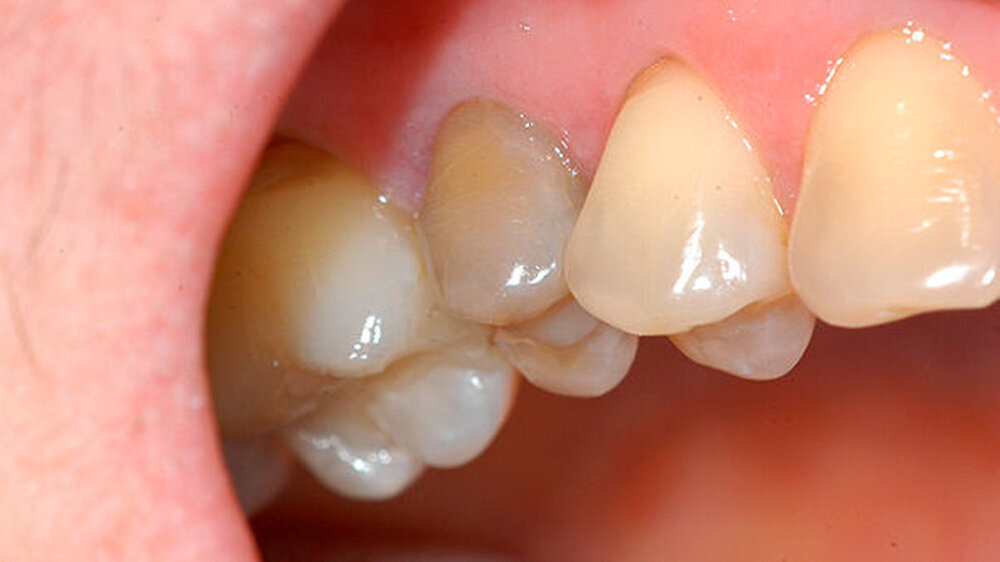

Danach wurden die Wurzelkanalwände des jeweiligen Fragments mit einem diamantierten torpedoförmigen Schleifkörper präpariert, wobei die Frakturflächen nicht berührt wurden (Abbildung 4). Auf die beiden Frakturflächen sowie die Wurzelkanalwände wurde anschließend ein selbstätzender All-In-One Dentinhaftvermittler (Optibond All-In-One; Kerr, Orange, USA) appliziert und die zwei Fragmente mithilfe eines dualhärtenden Komposits (Nexus NX 3; Kerr) adhäsiv zusammengesetzt (Abbildung 5).